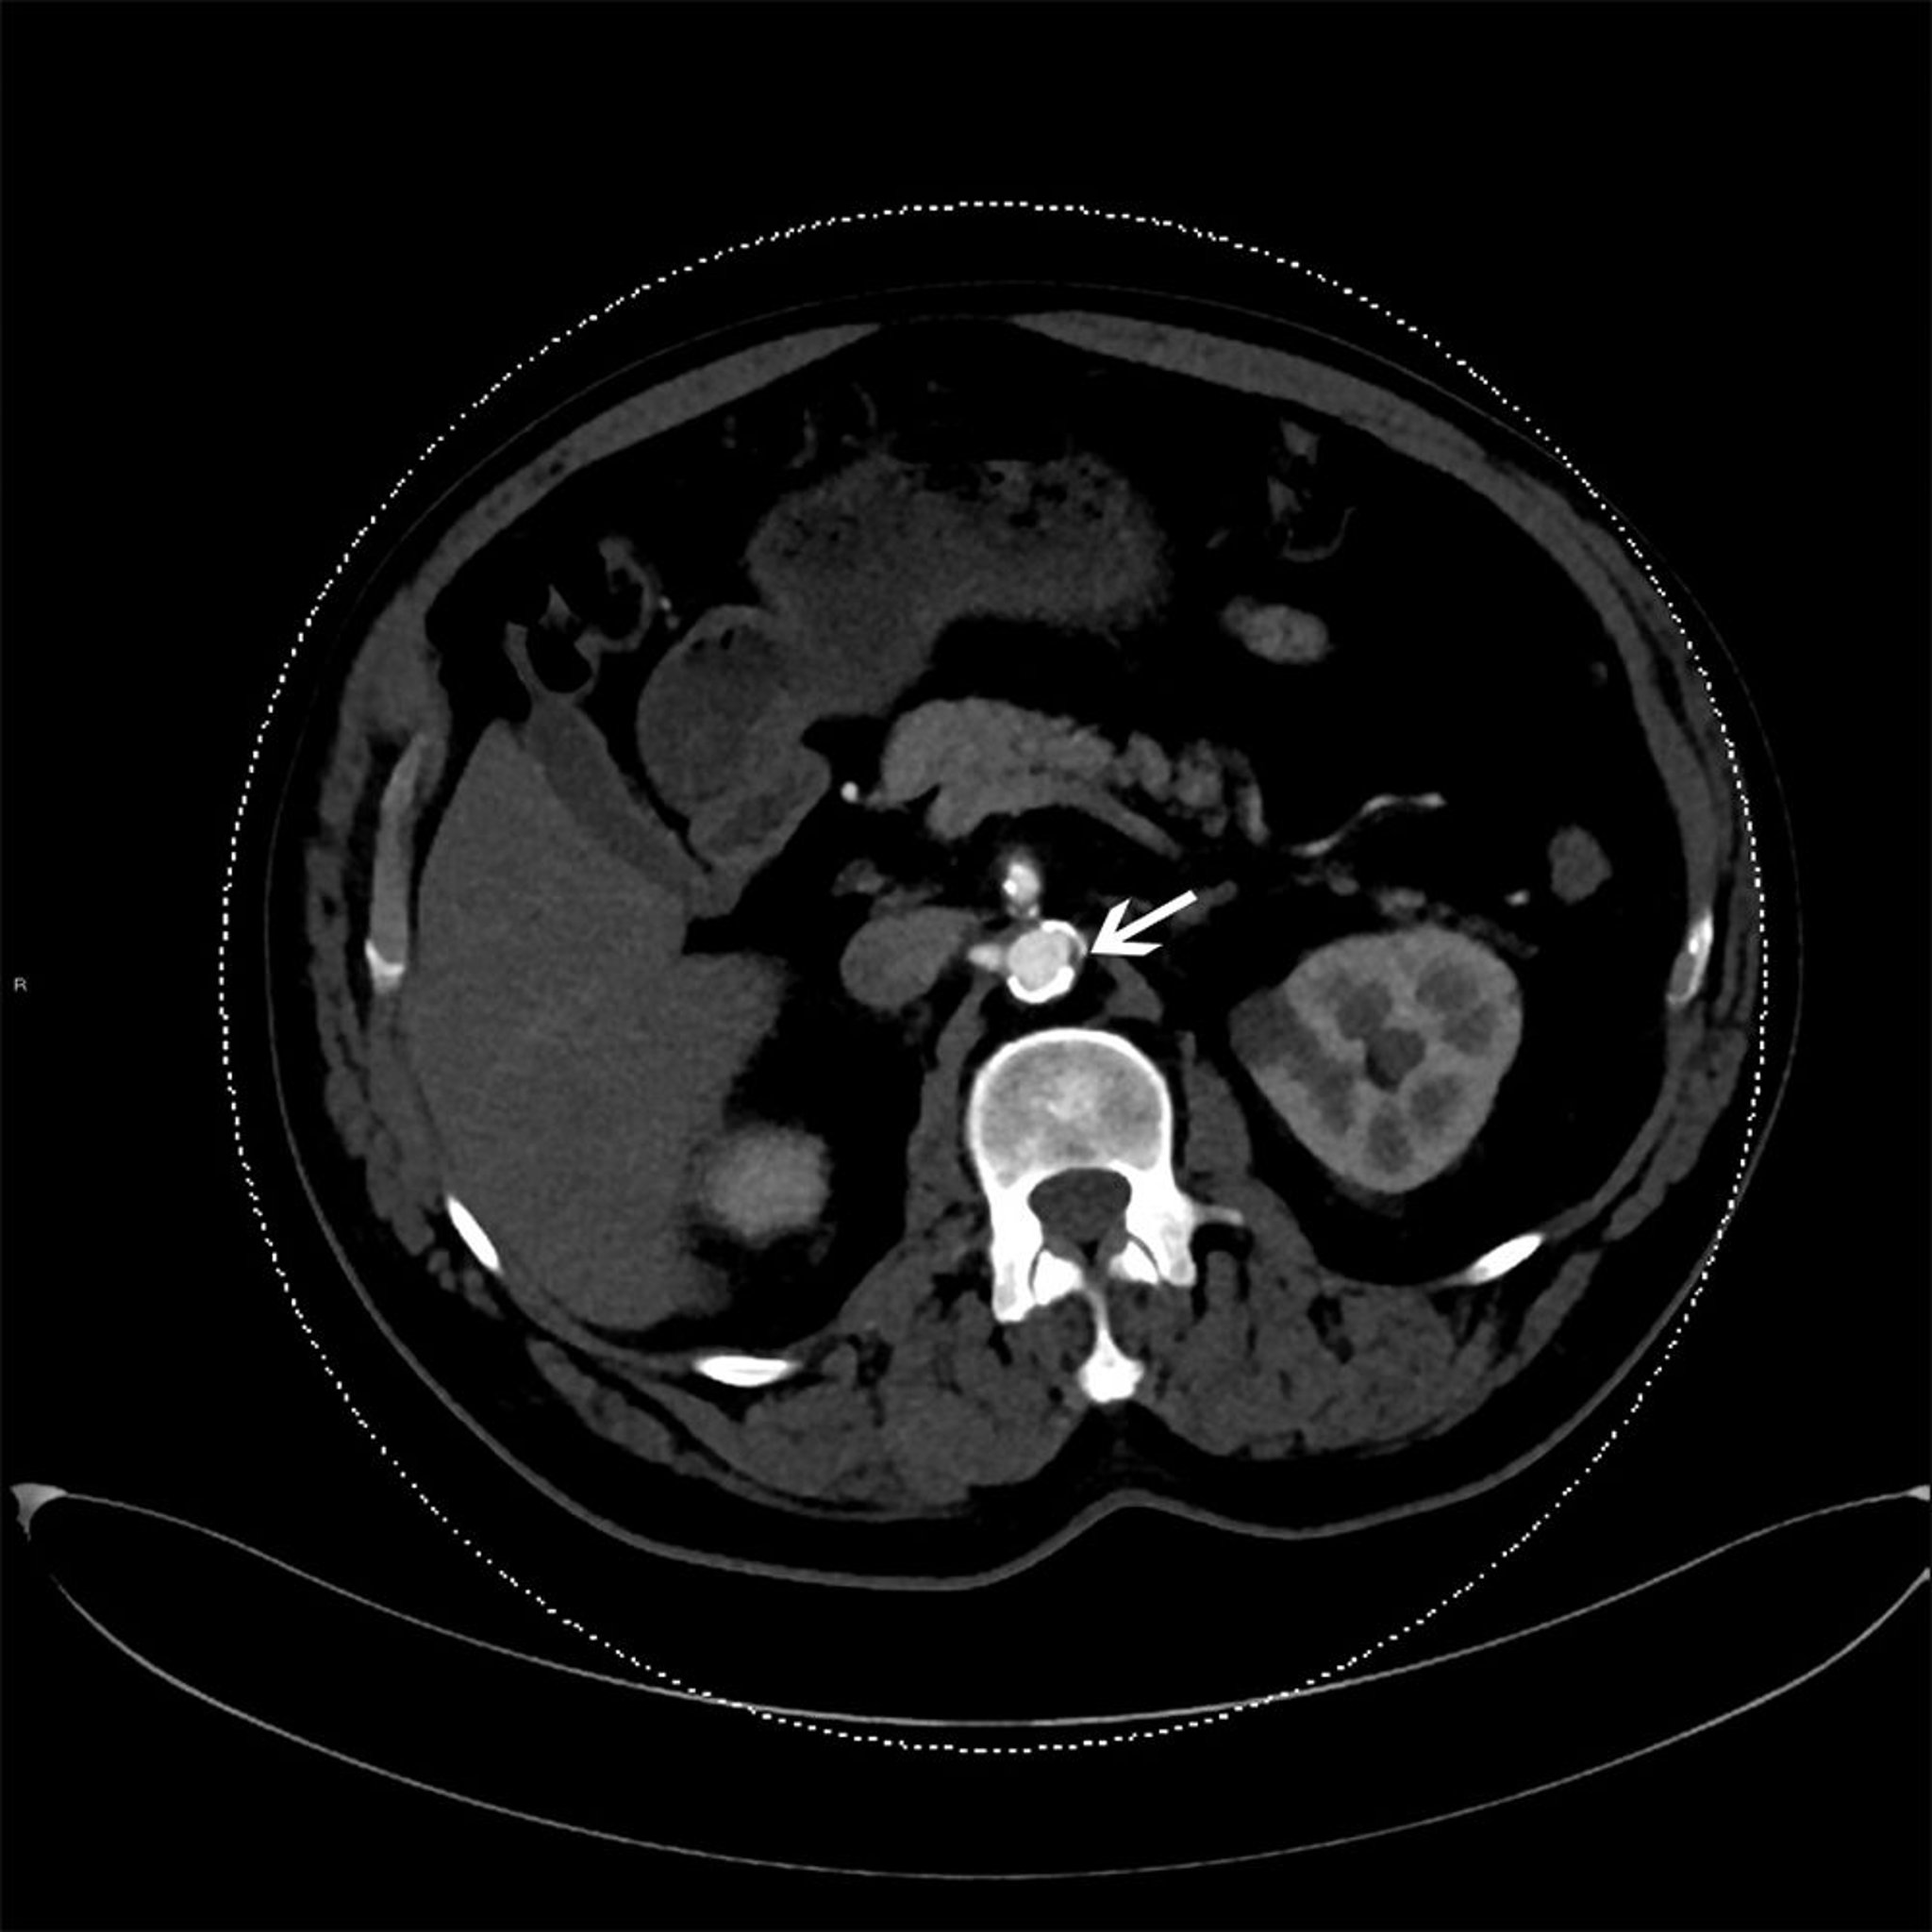

На снимке КТ с контрастным усилением показана атеросклеротическая бляшка в нисходящей части аорты (указана стрелкой).